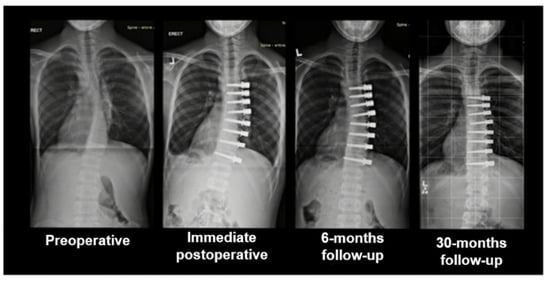

Video-Assisted Thoracoscopy for Vertebral Body Tethering of Juvenile and Adolescent Idiopathic Scoliosis: Tips and Tricks of Surgical Multidisciplinary Management

2. Materials and Methods

3. Results